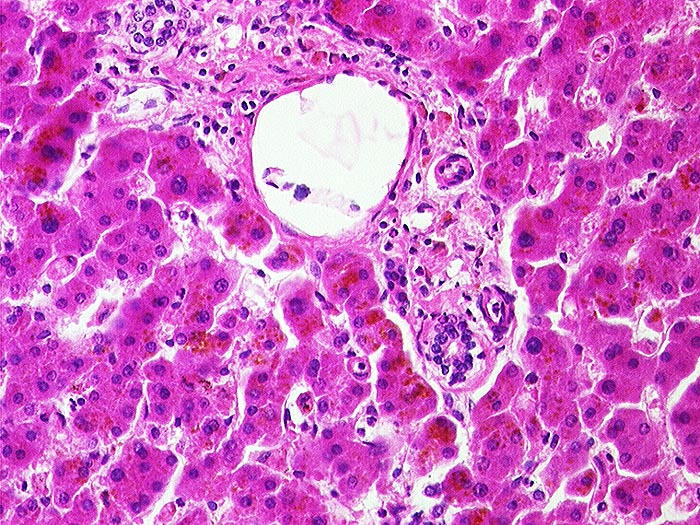

AP/ Leber bei Phenacetinabusus

Leber bei Phenacetinabusus

Leber